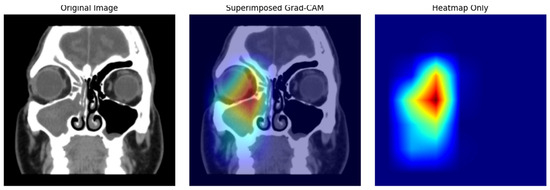

5. Grad-CAM Visualization

Interpretability is an important aspect of building trust with artificial intelligence systems in medical imaging. To address this, Gradient weighted Class Activation Mapping (Grad-CAM) [42] was used to visualize and interpret the predictions made by the proposed hybrid deep learning model. It gives visual explanations by highlighting the regions in an image that most contributed to the model’s predictions using Grad-CAM. The saliency maps bridge the gap between algorithmic output and clinical understanding of maxillary sinus conditions, and can be used as a tool for validation that the model is classifying the maxillary sinus condition using anatomically relevant structures.

Finally, the heatmap is superimposed on the original CT image using a color gradient, typically ranging from blue (low importance) to red (high importance). This overlay visually indicates where the model is attending when making its prediction, thereby enhancing interpretability.

5.2. Implementation and Representative Sampling

For consistency and diagnostic relevance, the final convolutional layer of the EfficientNetB0 network was selected as the target layer due to its high semantic content and retained spatial resolution. Representative CT images from all four classes—Normal Maxillary Sinus (MS), Opacified MS, Polyposis, and Retention Cysts—were selected for Grad-CAM analysis. Post-processing techniques, including heatmap thresholding, were applied to reduce visual noise and to sharpen the focus on medically relevant anatomical structures.

In Retention Cysts, the heatmaps displayed sharply localized activations along cyst margins, while Normal MS scans exhibited diffused, low-intensity activations across the sinus region, accurately reflecting the absence of pathology. Figure 8 presents the Grad-CAM heatmaps for Retention Cysts cases.

Figure 8. Grad-CAM heat maps Retention Cysts.